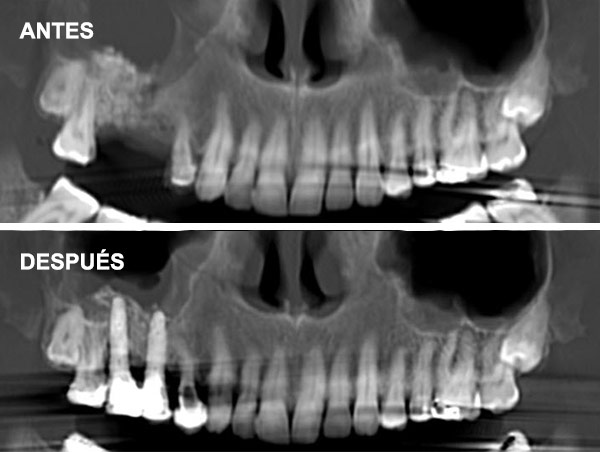

Se coloca una membrana y un injerto de hueso liofilizado, un compuesto de procedencia bovina que actúa como osteoinductor (Bio-Oss), así una vez colocado induce al hueso a formar nuevas células. Lo que se intenta hoy en día es encontrar una buena calidad de injerto para acortar el período de formación de hueso. También se coloca una membrana sobre este injerto.

Hay muchos biomateriales para inducir la formación de hueso, de distinta calidad y técnica en la elaboración.

En Clínica Sada, utilizamos el mejor biomaterial que científicamente está demostrado para la formación de hueso, Bi-Oss.